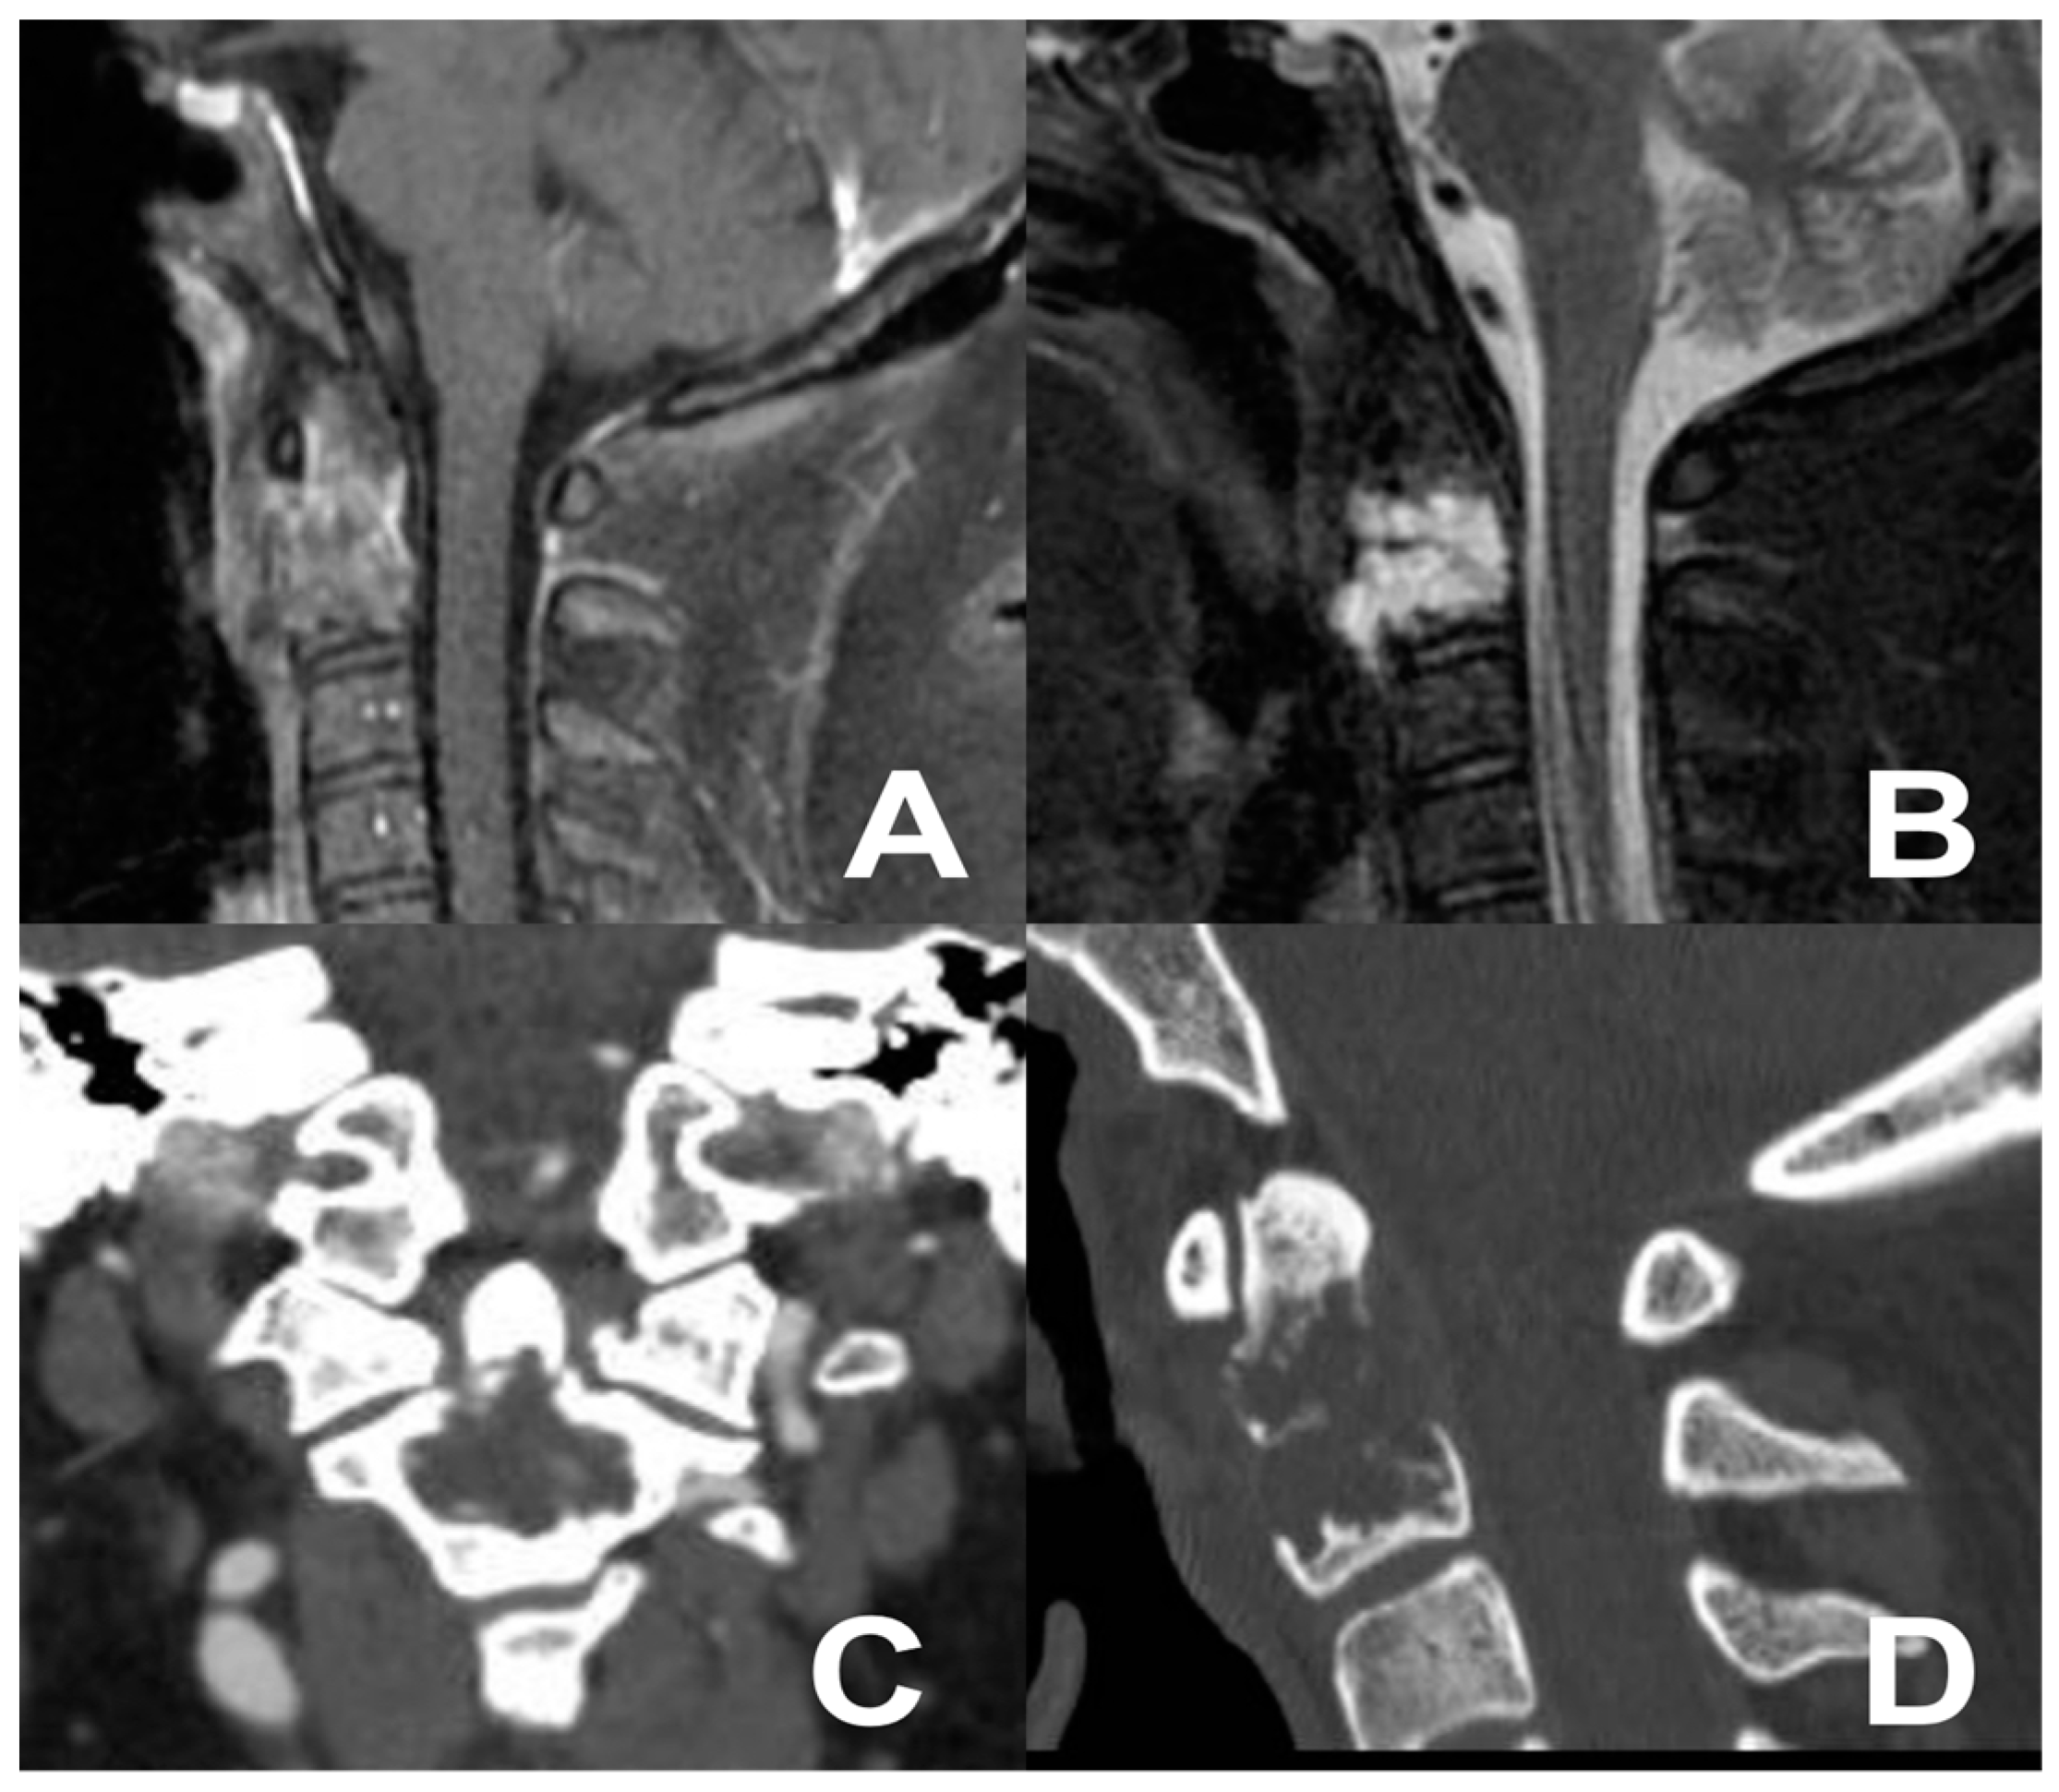

3.3. Second Case: One-Stage Combined Submandibular Retropharyngeal Approach and Posterior Midline C1-C2 Fusion